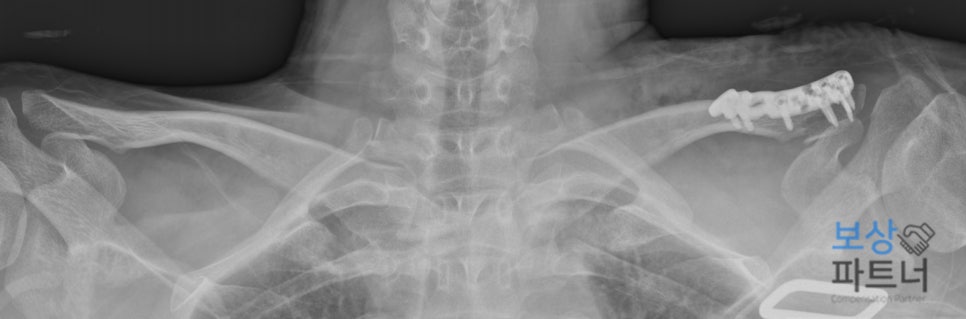

오늘 소개해 드릴 사례는 내리막길 주행 중 브레이크 고장으로 '쇄골 원위부 골절' 진단을 받은 30대 남성 의뢰인의 이야기입니다. 보험사와의 치열한 공방 끝에 최종 합의금 3,200만 원을 수령하게 된 과정과, 여러분이 꼭 알아야 할 보상 핵심 포인트를 상세히 짚어드리겠습니다.

상단에 첨부한 사진은 실제 의뢰인의 X-ray 영상인데요.. 빨간 박스로 표시된 부분이 바로 쇄골 원위부입니다.

전위가 심해 보존적 치료가 어렵다는 소견이 있었고 금속 플레이트와 나사를 이용한 고정술을 시행 받으셨습니다. 다행히 수술은 성공적이었으나 다친 부위가 어깨 관절의 움직임과 밀접하게 연관되어 있었습니다.

이런 경우 수술 이후에도 팔을 들어 올리거나 뒤로 젖히는 동작에서 운동 제한(강직)이 남을 가능성이 매우 높은데요.